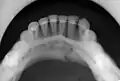

multiple mandible fractures of a patient in the right condyle (extracapsular/neck/not dislocated), right body (vertically unfavourable) and left coronoid process

Panoramic radiographs are tomograms where the mandible is in the focal trough and show a flat image of the mandible. Because the curve of the mandible appears in a 2-dimensional image, fractures are easier to spot leading to an accuracy similar to CT except in the condyle region. In addition, broken, missing or malaligned teeth can often be appreciated on a panoramic image which is frequently lost in plain films. Medial/lateral displacement of the fracture segments and especially the condyle are difficult to gauge so the view is sometimes augmented with plain film radiography or computed tomography for more complex mandible fractures.